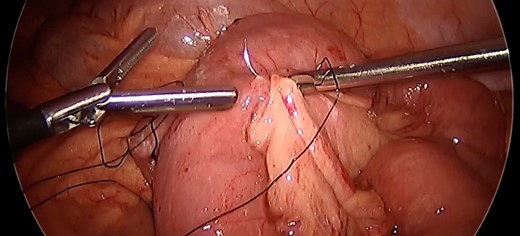

Laparoscopic survey revealed an ante-gastric retrocolic Roux limb. There was no internal hernia at the mesocolon. There was no Peterson’s defect. The enteroenterostomy was dilated. There was no intussusception at the time of exploration; however, the distalmost end of the Roux limb was easily invaginated into the enteroenterostomy with the lead point at the anastomosis. (Fig. 2) On the opposite side of the enteroenterostomy, the common channel limb could likewise easily be invaginated into the enteroenterostomy. There was no evidence of necrosis.

Intussusception. Surgeon manually demonstrating the propensity of the common limb to intussuscept into the anastomosis.